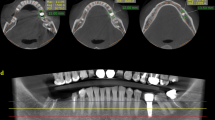

For the acquisition of CBCT images, an acrylic device with 16-cm diameter (Fig. 1a) was manufactured to attach to the support of the machine and allow the standardized positioning of the phantoms and location of the FOV. The phantoms were then scanned using an OP300 Maxio CBCT unit (Instrumentarium, Tuusula, Finland), operating at 90 kV, 0.085 mm voxel size, 8 × 6 cm FOV. The tube current was set at four different levels: 4 mA, 6.3 mA, 8 mA and 10 mA. The metal artefact reduction (MAR) tool was disabled during the acquisition of the exams. After each acquisition without MAR, new reconstructions of the same raw data were obtained with the activation of MAR algorithms.

After the acquisition of the initial images (i.e., mandibles without implants), 3.75 × 13 mm titanium implants (HE Conico - Intraoss, São Paulo - Brazil) were installed in 5 mandibles, and 3.3 × 12 mm zirconia implants (Pure Ceramic - Straumman , Basel - Switzerland) in the other 5 mandibles. All implants were inserted in the edentulous region corresponding to tooth 46. The portion of the ballistic gelatin covering the region was removed, an osteotomy following a sequence of drills recommended by the manufacturers was performed, and the implant was inserted manually using a ratchet. After implant placement, new gelatin was poured to refill the removed portions.

The phantoms with the implants were then scanned using the same scanning parameters described above. Therefore, a total of 160 exams were acquired (10 phantoms x before/after implant placement × 4 different tube currents x with/ without MAR—Fig. 2). Axial slices were exported in DICOM format for analysis using ImageJ (National Institutes of Health, Bethesda, MD, USA) based on the study of Fontenele et al. (2018).

Image assessment

Regions of interest (ROI) in the homogeneous regions (i.e., ballistic gelatin) were selected at the level of the implants to assess the effect of tube current on artefacts, which occur along the direction of the x-ray projection. In the axial slice in which the condensation silicone block was first visualized, a line was determined in the center of the implant and following the long axis of the mandibular body on the right side. Additional lines were then determined at different angles from the first line (65°, 90°,115°, and 140°). From the center of the implant, three semicircles with radii of 1.5, 2.5, and 3.5 cm were drawn. Finally, twelve 2.8 × 2.8 mm regions of interest (ROI) were established at the intersection of the circles and lines (Fig. 3). Mean (M) and the standard deviation (SD) of the gray values were registered for each ROI. The macro-function of ImageJ was used to determine and evaluate the same ROIs of each phantom in different conditions. An additional ROI was determined in the condensation silicone block to serve as a control area for the calculation of the contrast-to-noise ratio (CNR) according to the formula below [12]. Lower SD and higher CNR are associated with better image quality.

Regions of interest in the ballistic gel (1–12) and silicone block (13). Initially, a reference line was drawn along the long axis of the hemimandible and passing through the center of the implant. Additional lines were then determined at 65°, 90°,115°, and 140° (dotted lines) from the reference line. Three semicircles with radii of 1.5, 2.5 and 3.5 cm (dotted curves) were drawn from the center of the implant. Finally, the center of the twelve ROIs was determined at the intersection of the circles and lines (adapted from Fontenele et al., 2018)